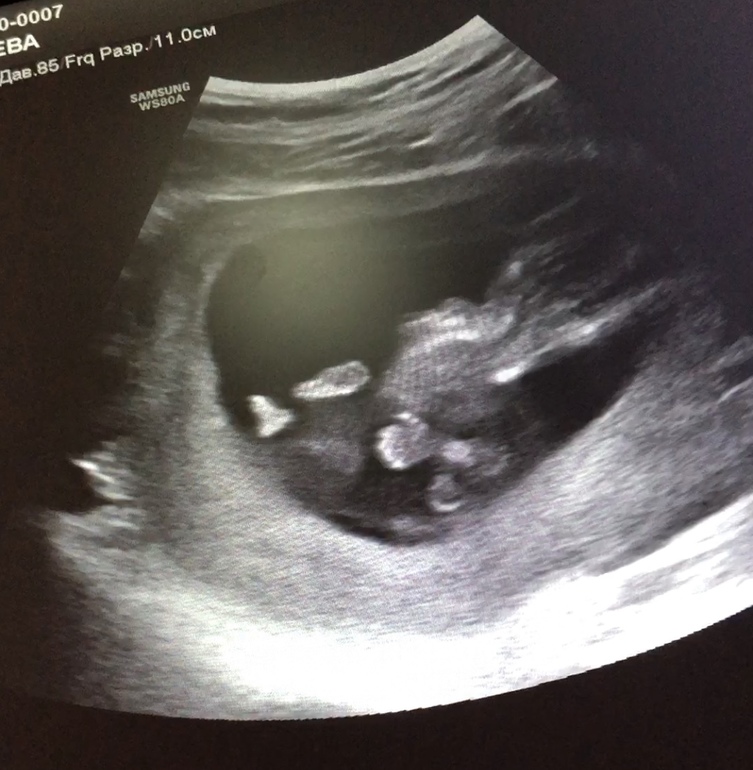

А вот человек, который показывает 👍😃